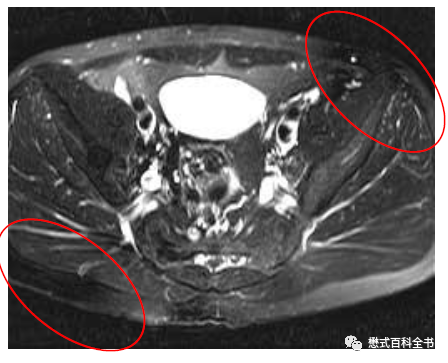

图16~18:线圈及单元故障导致的伪影

对于多通道线圈,如果某些单元或者通道产生故障,则对应的位置图像信号有异常。一般通过更换线圈、排查能够识别。

解决这种伪影当然从源头入手,更好线圈或者维修线圈。